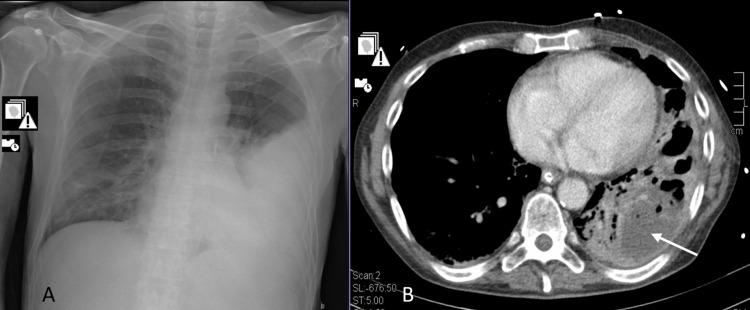

Pneumococcal infection is still a frequent disease. It can be classified as invasive when pneumococcus is isolated in a generally sterile fluid. Pneumonia is the most common infectious source of adult invasive pneumococcal disease (IPD), and several risk factors for IPD are well known. This case report presents three clinical cases of different manifestations of IPD. The two most severe cases had coinfection by SARS-CoV-2 at hospital admission.

肺炎球菌感染仍然是一种常见疾病。当在通常无菌的液体中分离出肺炎球菌时,可将其归类为侵袭性感染。肺炎是成人侵袭性肺炎球菌病(IPD)最常见的感染源,并且IPD的几种危险因素已为人熟知。本病例报告展示了IPD不同表现形式的三例临床病例。其中两例最严重的病例在入院时合并感染了SARS-CoV-2。